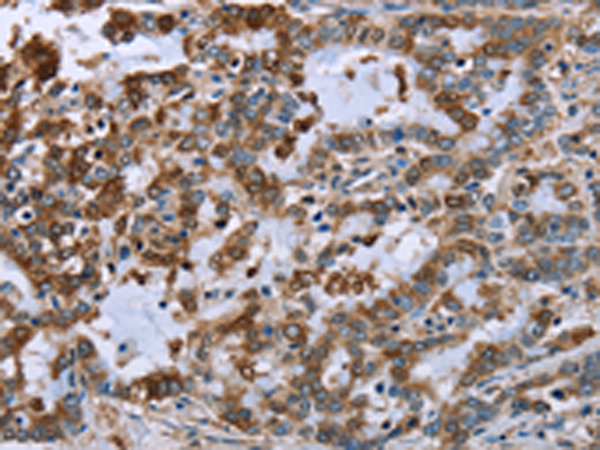

分类: 科研抗体货号: P01508别名: GBP; ECHA; HADH; LCEH; MTPA; LCHAD; TP-ALPHA应用: WB,IHC反应种属: Human, Mouse, Rat